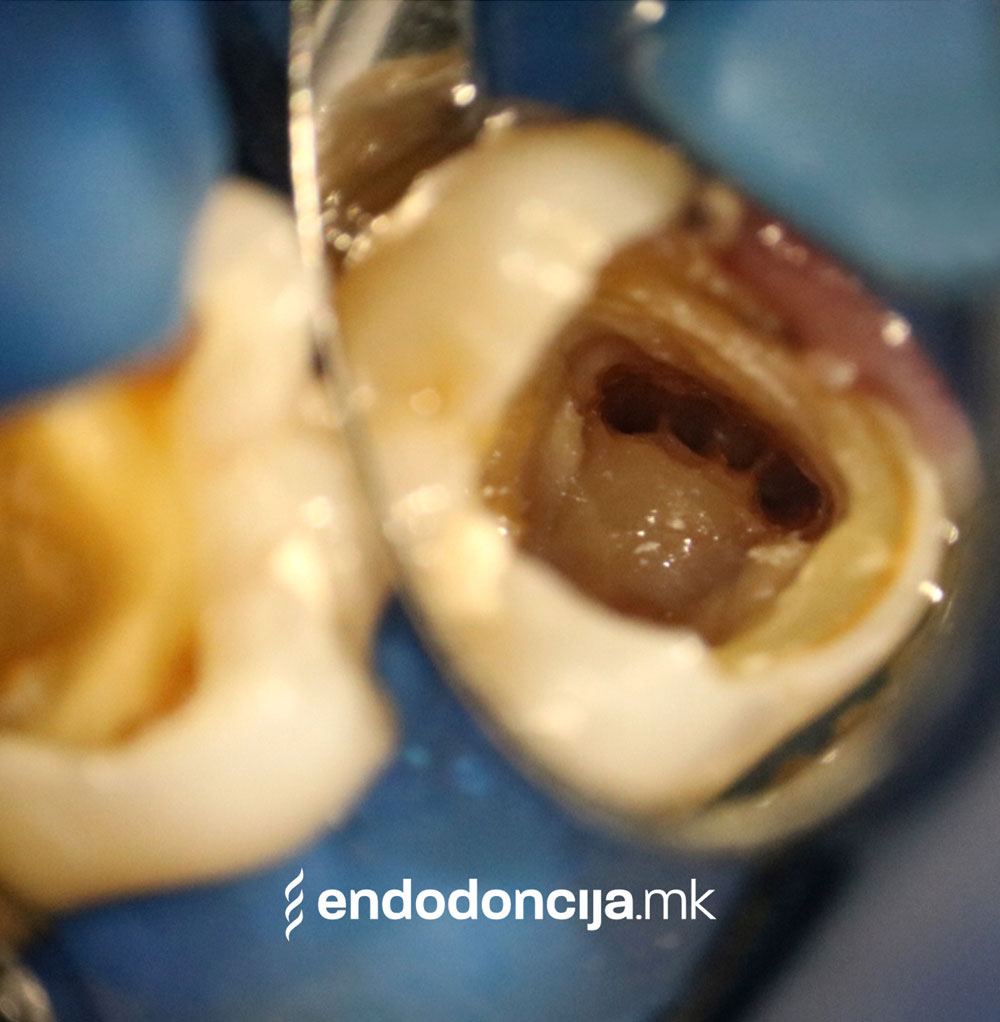

Она што е импресивно е прецизноста на микроскопските третмани. Дури и кога каналите се потешко достапни, може да се лоцираат и исчистат така што релапсите се со помала веројатност. Спротивно на тоа, скриените канали често остануваат неоткриени во конвенционалниот третман на коренскиот канал и затоа не можат да се чистат. Бактериите можат да се размножуваат таму без пречки и да предизвикаат воспаленија. Ова често останува незабележано со години додека не се појави забоболка, а со тоа и компликации.

Употребата на микроскоп исто така овозможува детектирање пукнатини или фрактури што може да предизвикаат болка или воспаление.